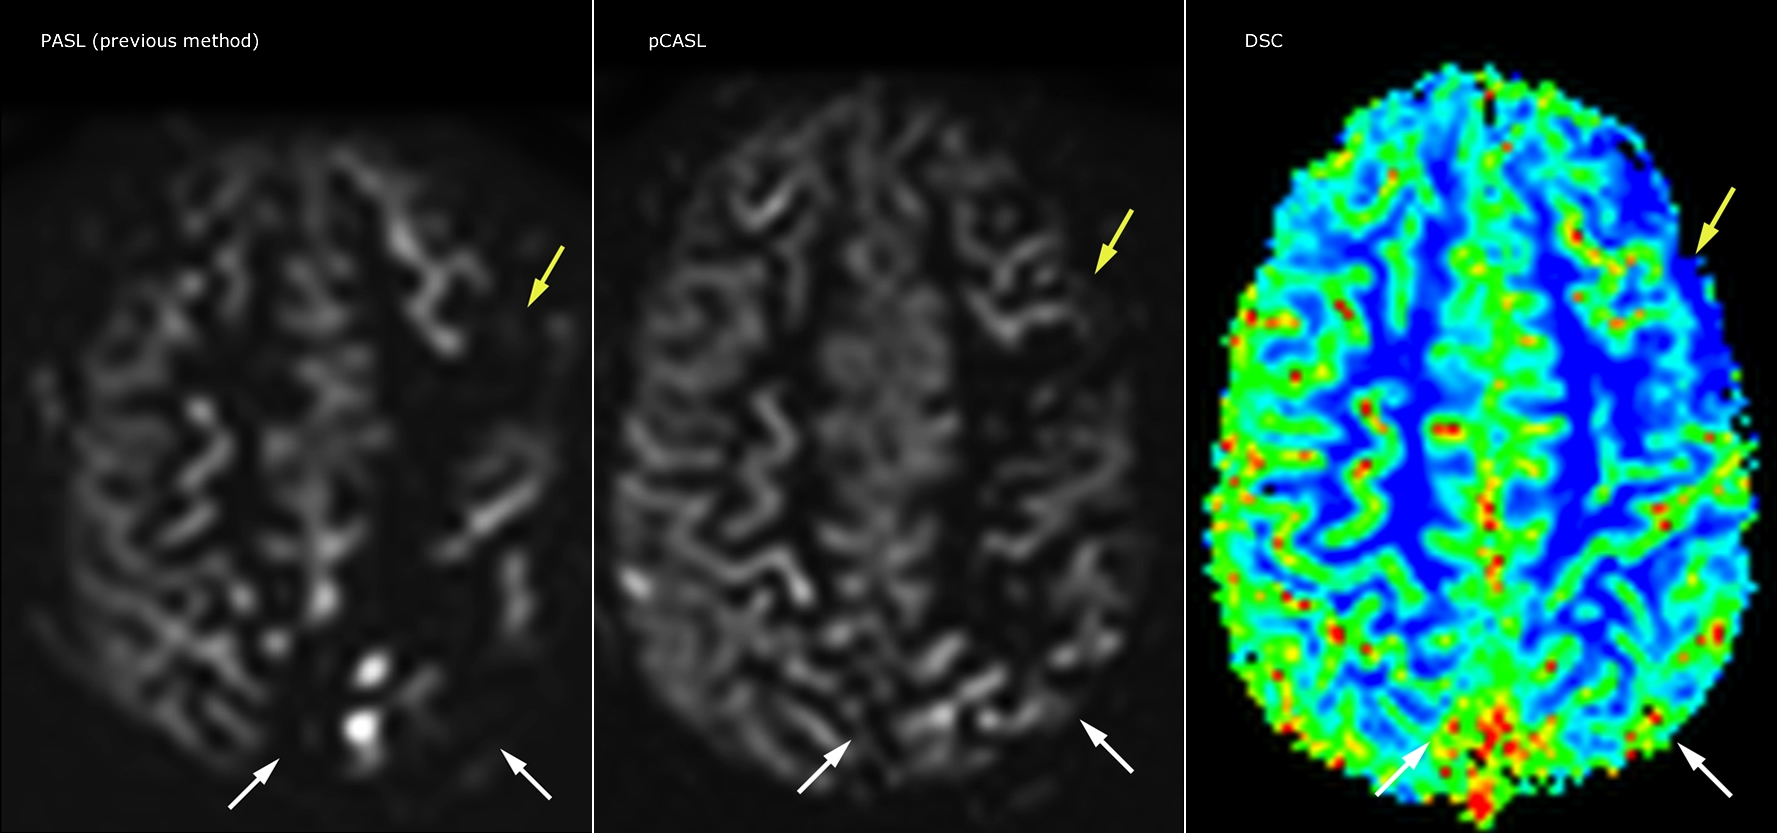

Pseudo-continuous arterial spin labeling (pCASL) was developed for brain perfusion imaging without contrast agent. “This is very desirable in pediatric patients where the general trend is to limit the administration of contrast,” says Dr. Miller. Growing confidence in specific applications “We built up confidence in pCASL by comparing it to contrast-based perfusion imaging. Once we had confidence that it was representing what the contrast perfusions were representing, we increased our diagnostic confidence by serial imaging in either the acute stage or the long term stages in a number of patients with arterial abnormalities.

Dr. Miller uses pCASL for all patients who present with chronic and acute cerebrovascular abnormalities such as acute stroke, as well as patients who present with signs of acute inflammation in the brain, and occasionally in patients with tumors, to assess the perfusion status of their tumor.

“In combination with diffusion weighted imaging, it can help give a more extended assessment of the degree of perfusion abnormality in a patient who is suffering acute ischemia. We have a number of patients who have chronic arterial insufficiency due to prior arterial abnormalities or acquired arterial abnormalities such as sickle cell disease or neurofibromatosis. Sometimes the child’s first manifestation of disease progression is a reduction in brain perfusion before stroke symptoms manifest clinically or in diffusion weighted imaging. We use pCASL to help delineate the perfusion abnormality.”

“pCASL has now become more of a first-line scan for assessing perfusion for us, as opposed to DSC-based perfusion imaging with contrast agent. And in patients who were not planned to have contrast, we can perform pCASL for perfusion imaging without need to stop the exam, pull the patient out, and put in an IV. It also negates the postprocessing that’s necessary for dynamic susceptibility contrasts. And it allows us to repeat perfusion imaging in the same patient at the same imaging time, which is helpful in terms of patient motion, or in a situation where a scan needs to be done before pharmacological perfusion imaging.”